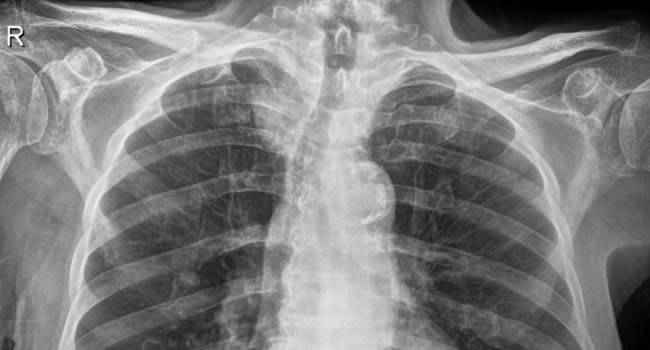

Οι ακτινογραφίες πραγματοποιούνται με πλήρως ψηφιακό εξοπλισμό και όχι ψηφιοποιημενο από έμπειρους Τεχνολόγους – Ακτινολόγους με άδεια ασκήσεως Επαγγέλματος.

Ο πιο σύγχρονος φορητός Ακτινολογικός εξοπλισμός πλήρως ψηφιακής απεικόνισης (DR) σε μια κινητή ακτινολογική μονάδα, μπορεί να επισκεφθεί τον ασθενή οπουδήποτε στην περιοχή της Θεσσαλονίκης και των περιχώρων και να σταλεί, αν ο ασθενής το επιθυμεί, η γνωματευμένη ακτινογραφία ηλεκτρονικά μέσω διαδικτύου στον θεράποντα- παραπέμποντα ιατρό ο οποίος θα λάβει το αποτέλεσμα στο προσωπικό του υπολογιστή, tablet, Smartphone οπουδήποτε κι αν βρίσκεται.